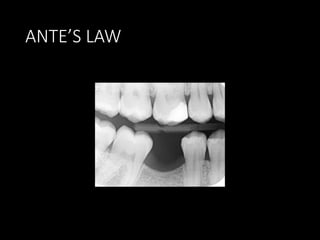

ANTE’S LAW

Periodontal Ligament Area

 Another consideration in the evaluation of prospective abutment

teeth is the root surface area or area of periodontal ligament

attachment of the root to the bone.

 Larger teeth have a greater surface area and are better able to

bear added stress.